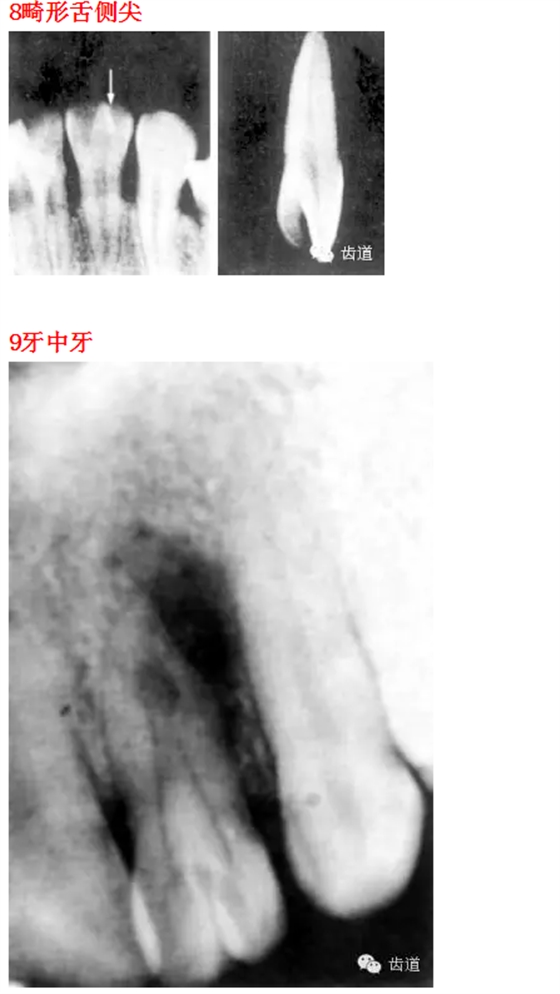

首頁(yè)口腔影像 26種口腔病變X光片

26種口腔病變X光片